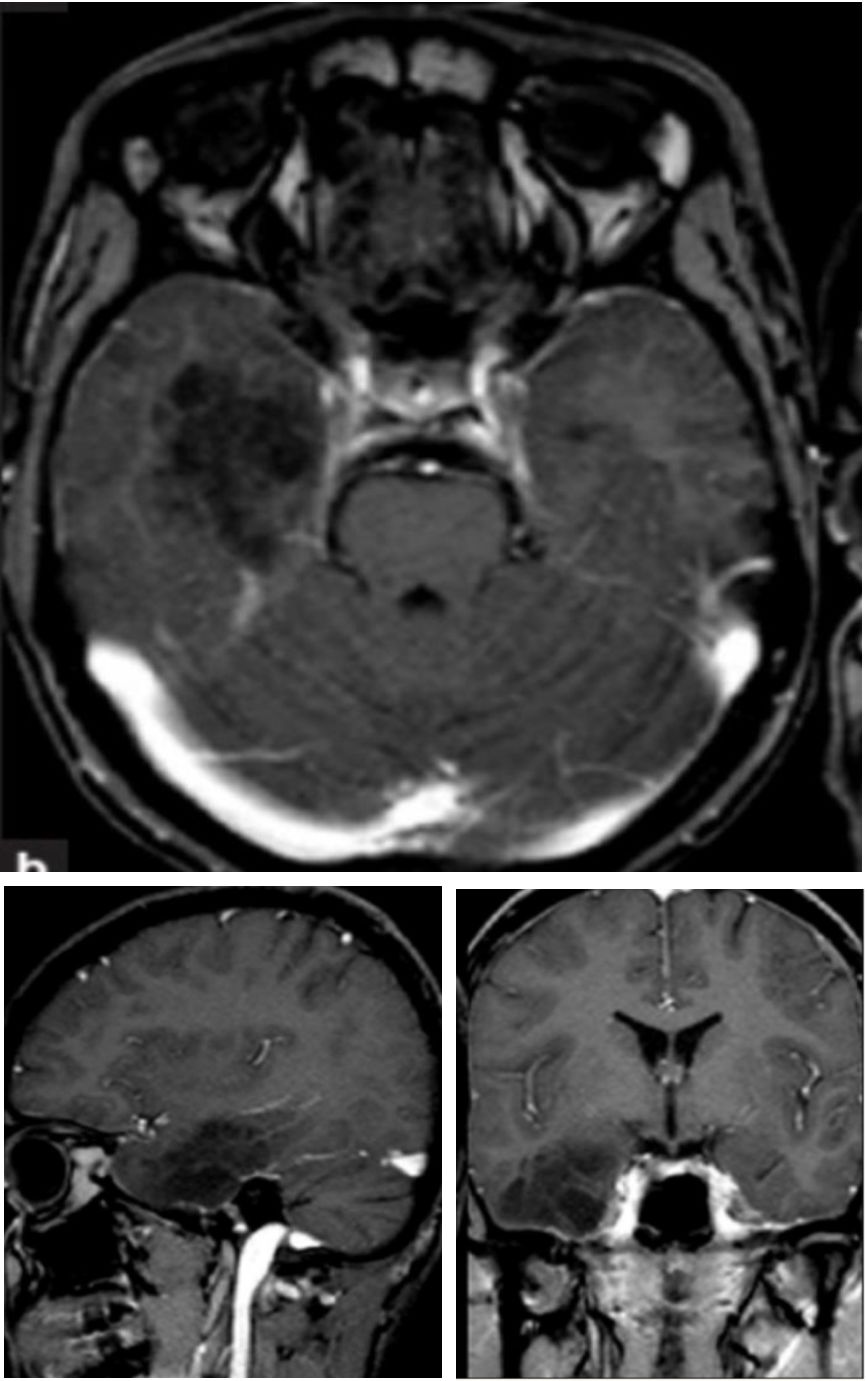

增强序列可见双侧额叶软脑膜明显强化并沿软脑膜侵入沟回,左侧颞顶交界区小片状强化;冠状位及FLAIR可见皮层皮下之白质亦有波及。该病例只有磁共振,且只有FLAIR和增强两个序列,但给人的信息量并不少:脑膜尤其是软脑膜受累突出,伴有皮层、实质损害,强化明显。感染、肿瘤、非感染性炎症都有可能,到底是什么呢?

诊断: 神经结节病

结节病是一种病因不明的多系统肉芽肿性炎症性疾病,年轻人多见。全世界的发病率各不相同,约为10-20/100,000人。它主要影响肺,皮肤和眼睛,神经系统受累约占5-20%。可以说神经结节病是罕见病中的少见表现,但其影像学具有一定的特点,也容易与其他疾病混淆,了解了这些特点在日后不期而遇时不会让它从眼皮下溜走。神经结节病影像学最突出的特点是软脑膜受累,但只知道软脑膜是不足以全面掌握神经结节的影像学表现,关于神经系统其他受累部位及鉴别诊断如下图:

这里摘选几张有代表性的影像:

➤脑实质受累(fig3:延血管间隙播散的炎性肉芽肿改变;fig5:脑白质病变):

➤表现为出血:

➤脑干胡椒粉改变:

➤脊髓受累:

五花八门的受累部位和表现让人看花了双眼,万变不离其宗,颅底为主的软脑膜受累以及沿血管间隙的强化,以及各种肉芽肿样强化,都应该考虑到神经结节病的可能,但因其少见,不要忘了最基础的诊断原则,首先应当谨慎与其他更常见的疾病相鉴别。